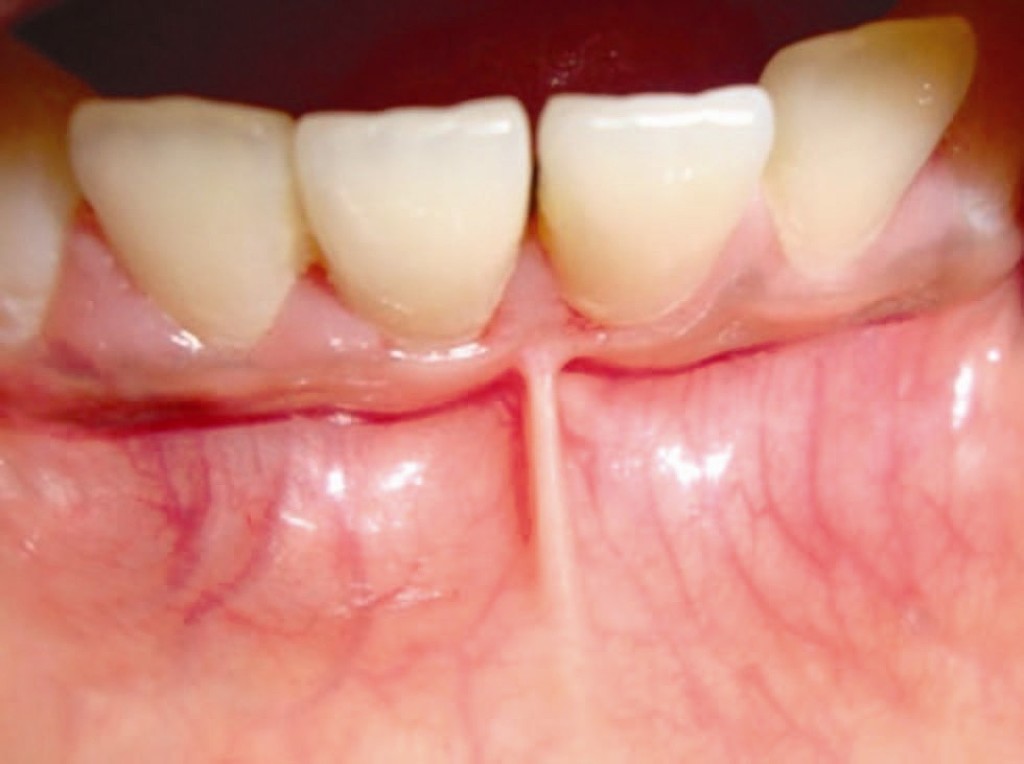

Frenulum In The Mouth

What Is A Frenum (Frenulum)?

In our mouth, most people have two groups of tissue called frenums found in and around the gums and teeth. It is a piece of really soft tissue that appears as a thin line between the gums and lips. You can find it on the top and the bottom of your oral cavity. There’s also a frenum that extends along the bottom of the tongue and connects to the bottom of the mouth just behind the teeth. Different people have different frenums. It can vary in length and thickness.

Labial frenum – This type of frenum is placed in the front of your mouth between the upper lip and gum. His counterpart is positioned between the lower gum and the lower lip. If there is an issue with this type of frenum, it can change the way your teeth grow in and can influence your dental health. Particularly it can pull your gums away from a tooth revealing the root.